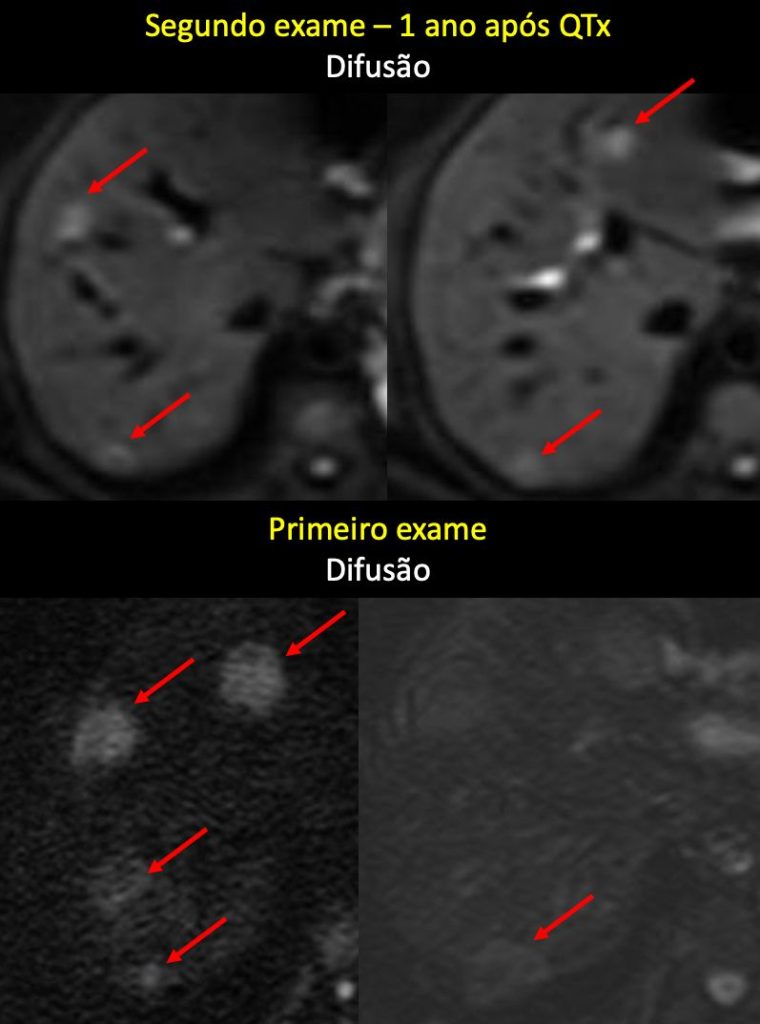

Análise evolutiva por ressonância magnética de metástases hepáticas pós-quimioterapia

A avaliação evolutiva por ressonância magnética (RM) do fígado em pacientes com metástases hepáticas de adenocarcinoma de cólon após quimioterapia é um passo fundamental na radiologia oncológica moderna. Em muitos casos, a redução do tamanho da lesão não é suficiente para definir resposta completa, pois lesões residuais podem corresponder a tumor viável, fibrose/cicatriz pós-tratamento ou necrose.